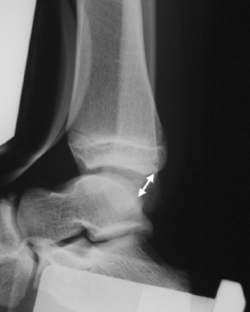

Fig. 2

Arthroscopic findings showed ATFL injury in 30 out of 34 cases. The diagnosis of ATFL injury with stress X-P, US, MR imaging were made with an accuracy of 67, 91 and 97%. US and MR imaging demonstrated the same location of the injury as arthroscopy in 63 and 93%.